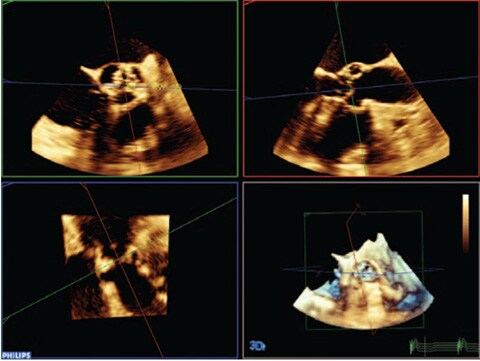

EPIQ 7 Es zeichnet sich durch höchste klinische Leistung zur Erfüllung der hohen Anforderungen in der heutigen kardiologischen Praxis aus.

Das Affiniti 70 Ultraschallsystem ist eine gelungene Kombination aus hervorragender Leistung und optimierten Arbeitsabläufen für eine schnelle und sichere Diagnosestellung.